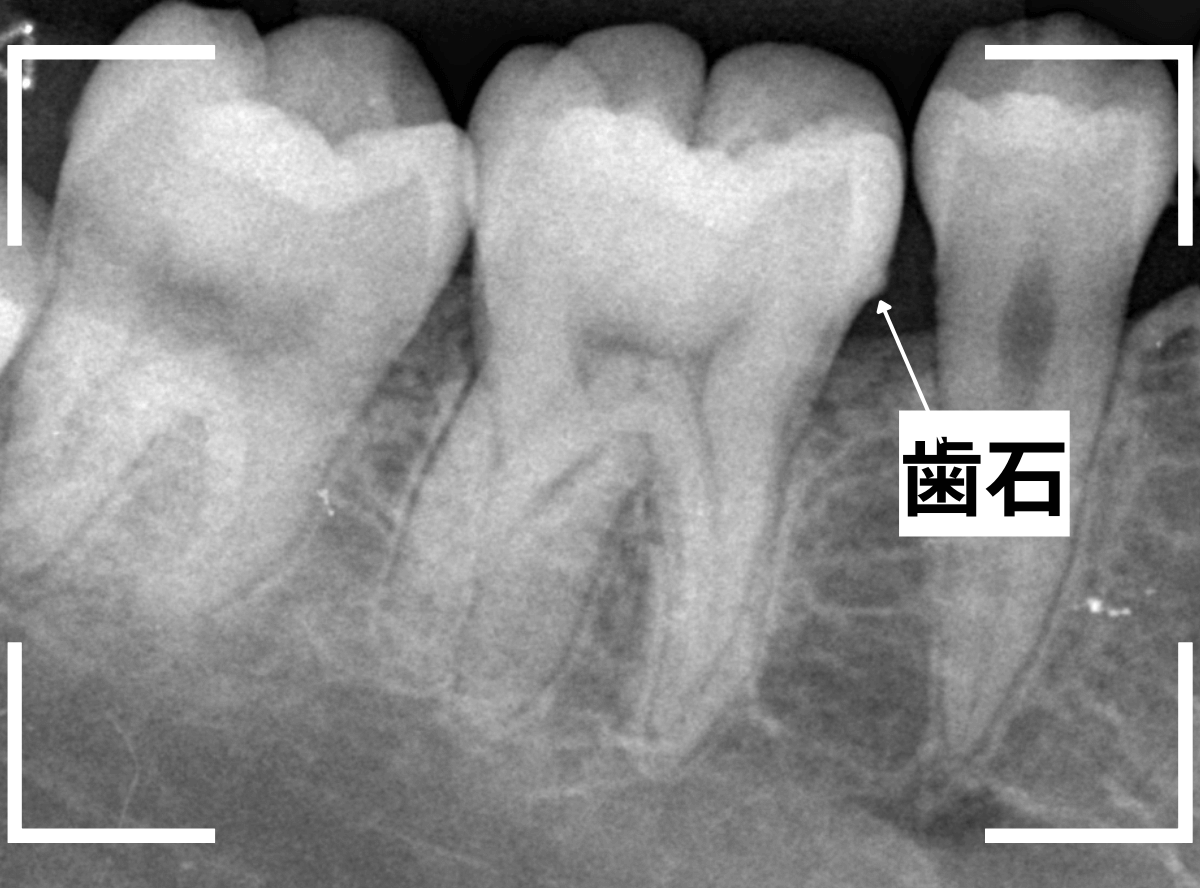

Case.4 レントゲンでわかりづらい、側面の虫歯

検診希望で受診された患者さんです。

歯の溝(裂溝)に虫歯がありそうな歯が見つかりました。

レントゲン写真で確認しますが、虫歯らしき写り方はしていません、浅い虫歯なのでしょうか。

関係ないですが、歯石は確認できますね。

あとは、歯の溝の虫歯を少しずつ除去しながら確認するしかありません。

すると、歯の側面に深めの虫歯が出てきましたので、慎重に虫歯を除去します。

全ての虫歯を除去しました。

今回のように、歯の側面の虫歯は、通常のレントゲン写真でわかりづらく、意外と深い虫歯になっている事があるので要注意ですね。

今回は、通常のレジン治療で終われました。

側面の虫歯を症状が出る前に見つけられたのが幸いでした。